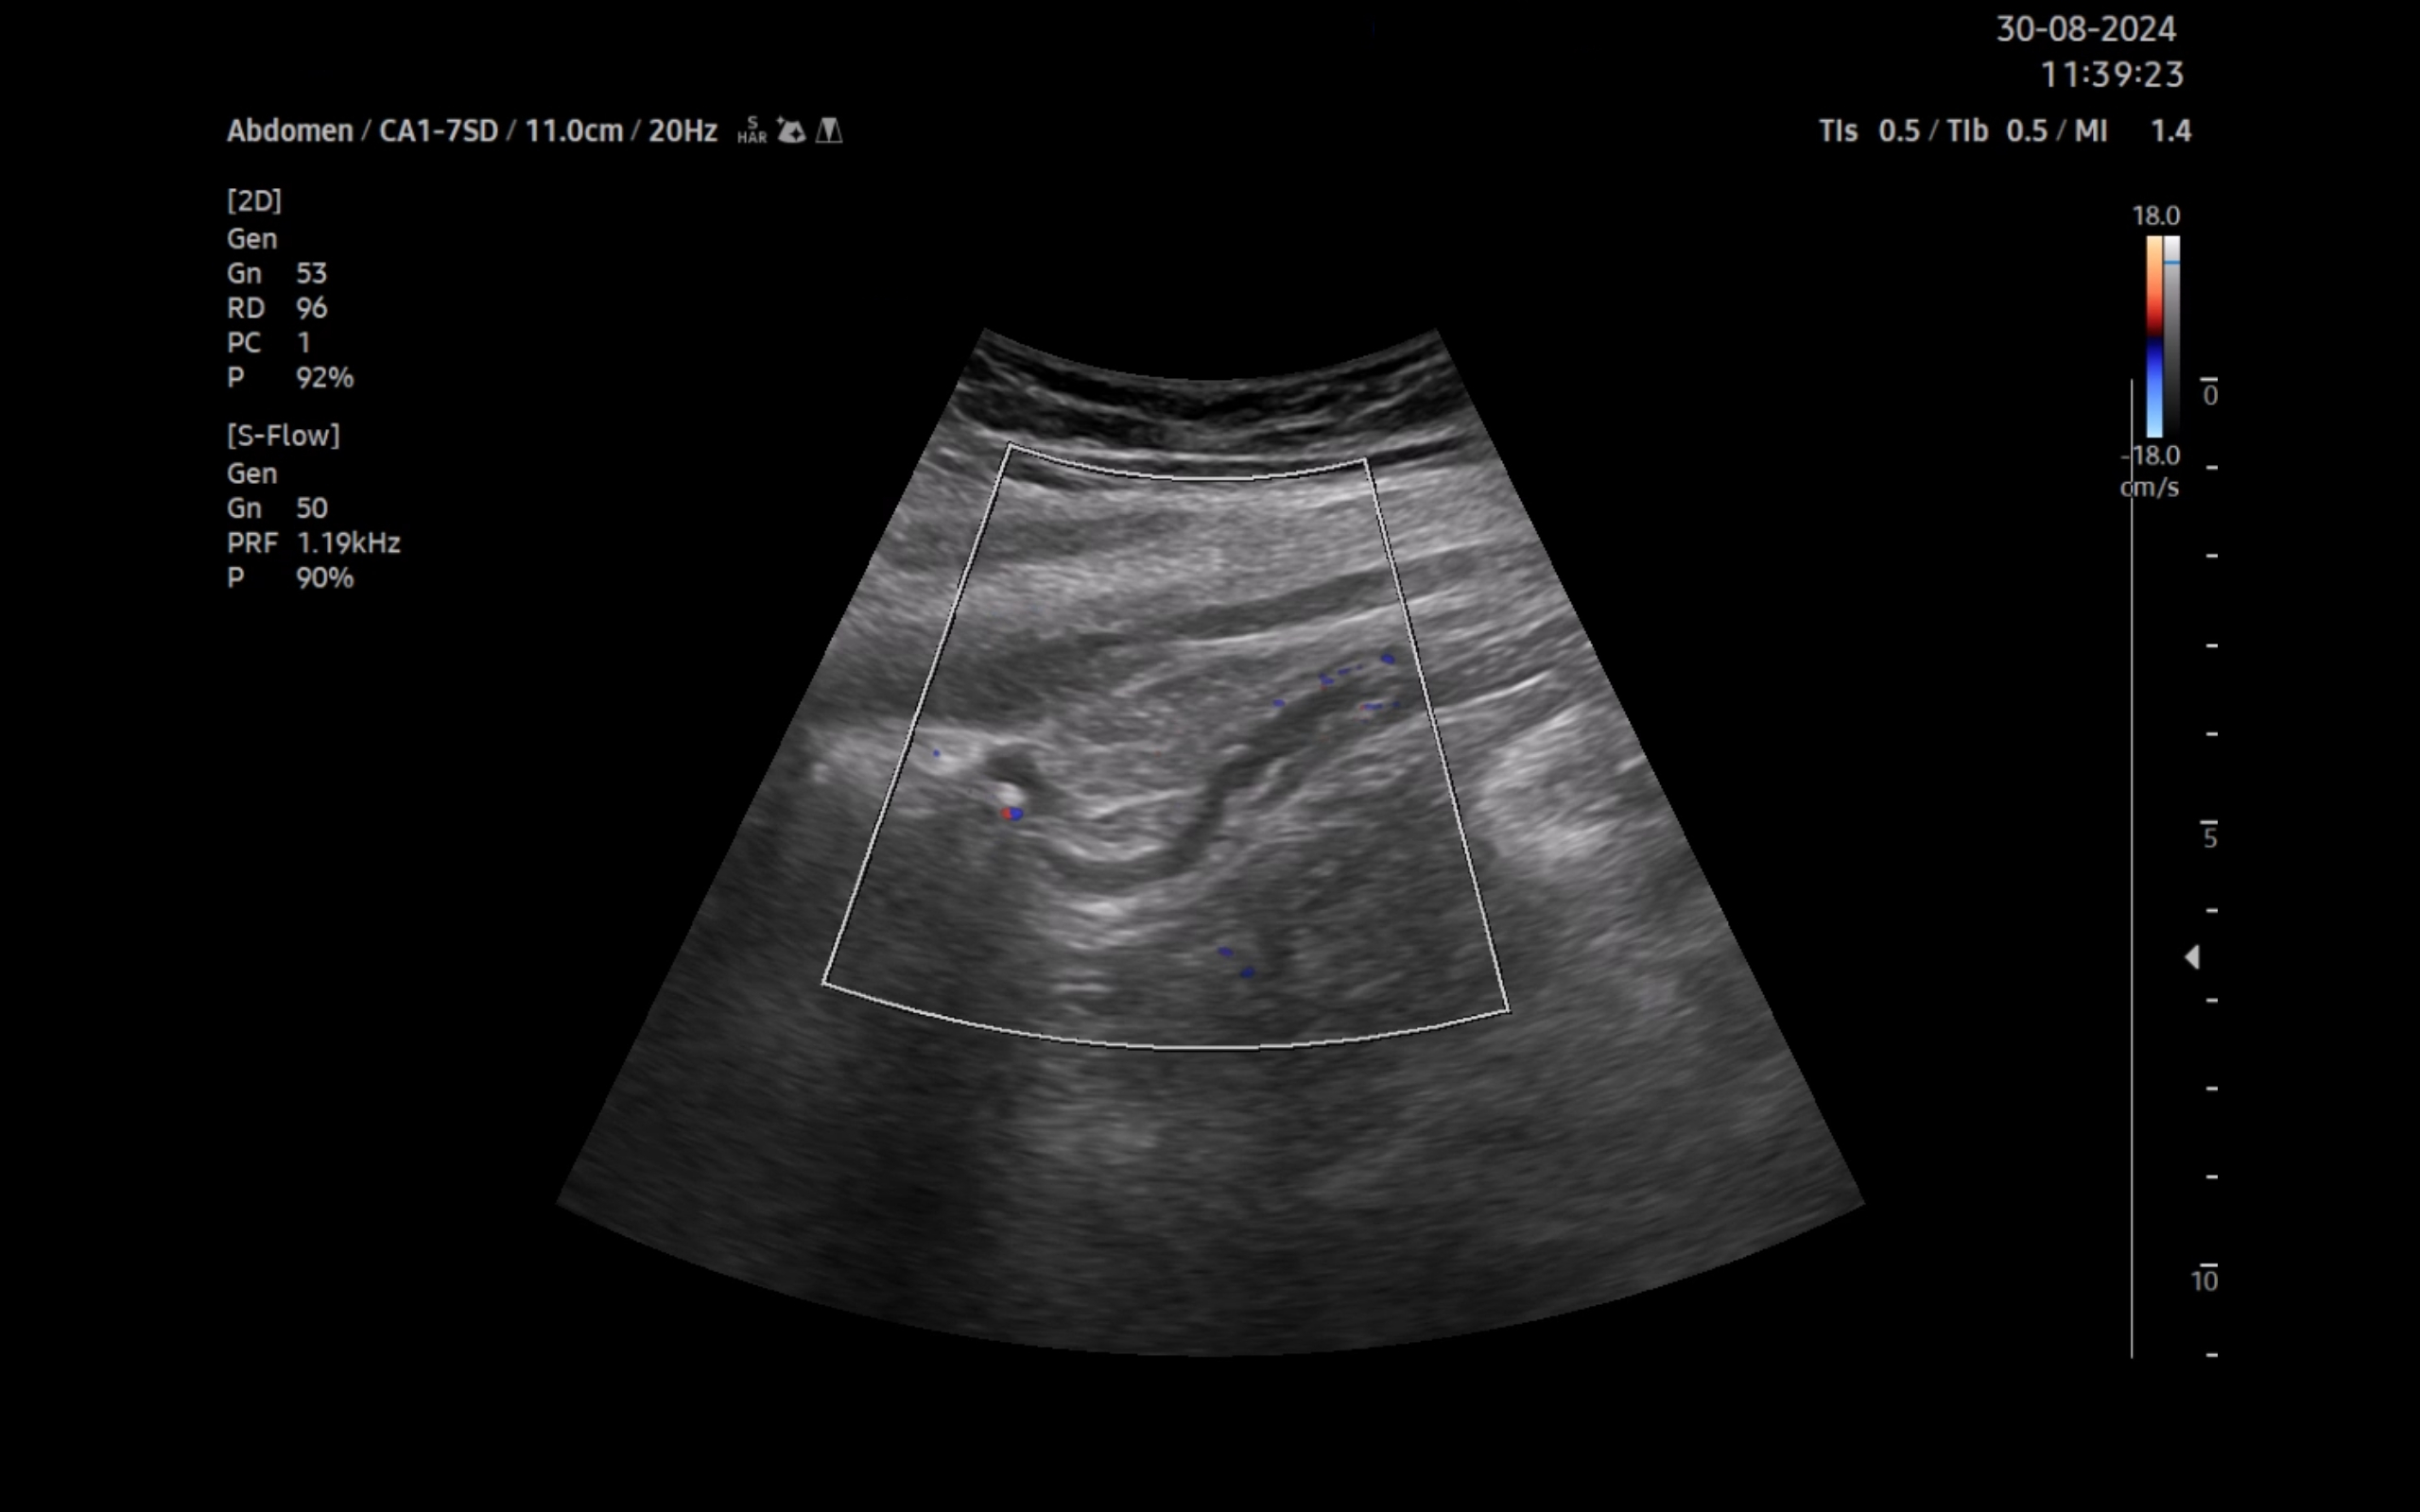

Ecografía clínica:

Imagen hiperecogénica con sombra en interior de vesícula biliar, hígado, páncreas, bazo y riñones sin alteraciones, vejiga orina poco replecionada. Llama la atención mínima imagen anecogénica en fondo de saco de Douglas. Apéndice visible en fid con diámetro 1,07 cm con captación aumentada con apendicolito con fenómeno centelleo.

La ecografía complementa la anamnesis y la exploración física. A día de hoy está disponible en la mayoría de centros de salud. En el caso concreto de la paciente, la discapacidad intelectual limitó la información obtenida de la entrevista. Ante la detección de un apéndice con diámetro mayor de 6 mm, no compresible, captación aumentada y apendicolito, se ha podido diagnosticar el proceso.